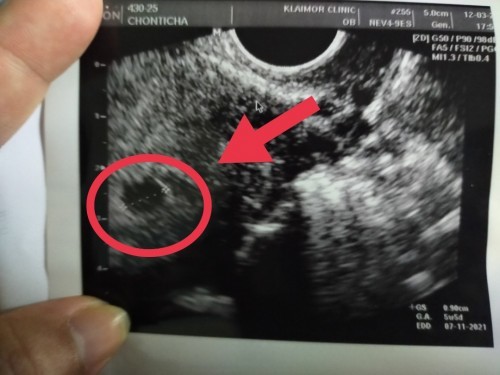

หมอซาวยังไม่พบเสียงหัวใจแต่เจอถุงการตั้งครรภ์ แม่ยังมีหวังมั้ยค่ะ